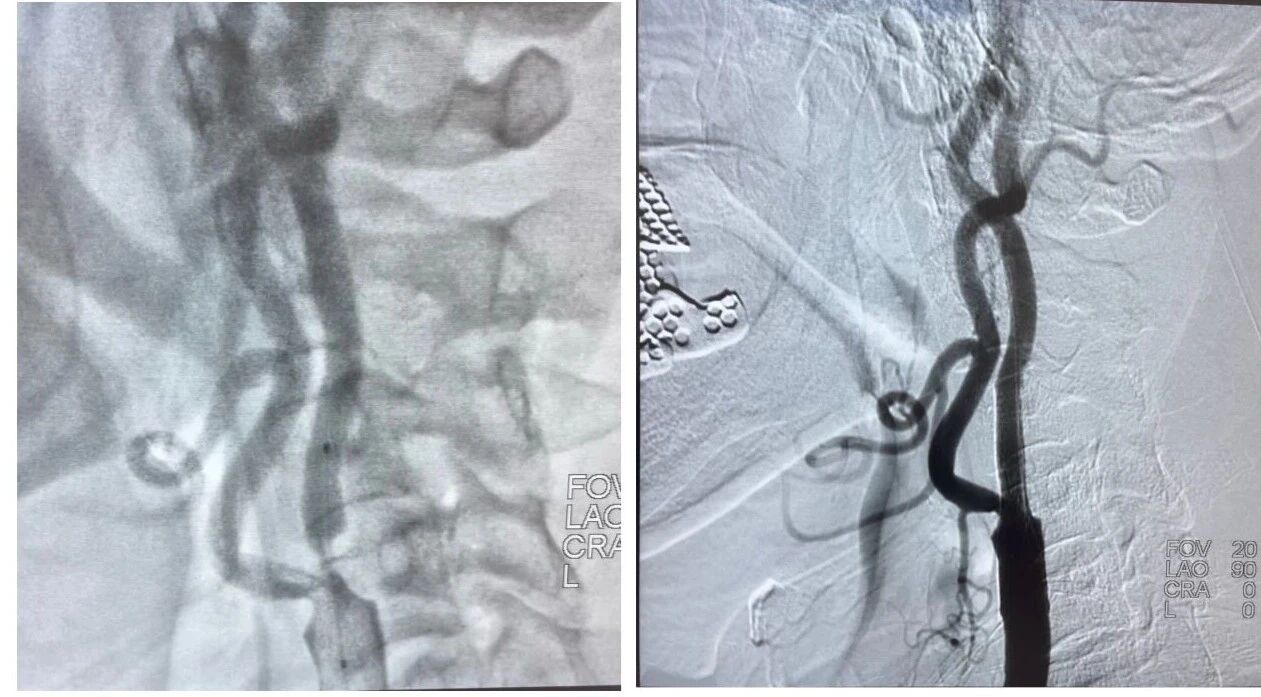

一位突发左侧肢体无力、言语不清的老年高龄患者被紧急送至医院,头颅CT检查提示急性缺血性脑卒中,脑血管造影显示右侧大脑中动脉主干完全闭塞,情况危急。

在介入手术室韩洪武主任、张镭护士长团队的配合下将微导管、取栓支架精准送达血管闭塞部位,顺利取出堵塞血管的血栓。术后造影显示,患者闭塞的血管完全开通,血流恢复通畅。经过后续的精心治疗和护理,患者左侧肢体功能逐渐恢复,现已能正常交流和自主活动。

患有严重脑血管狭窄的患者,反复出现头晕、肢体麻木症状,随时面临血管闭塞引发脑卒中的风险。赵旭主任为其完善脑血管造影检查,明确血管狭窄部位及程度后,为患者实施支架植入术。

手术中,赵旭主任精准定位狭窄血管,小心翼翼地将支架送至病变处并顺利释放,术后患者血管狭窄情况得到显著改善,头晕、麻木症状彻底消失,生活质量大幅提升。